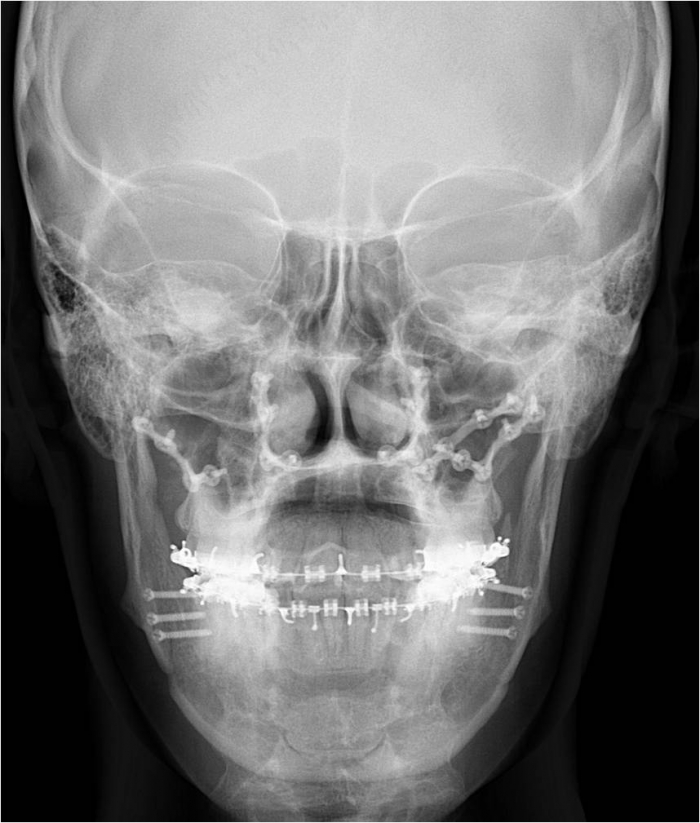

Telerradiografia frontal após a cirurgia